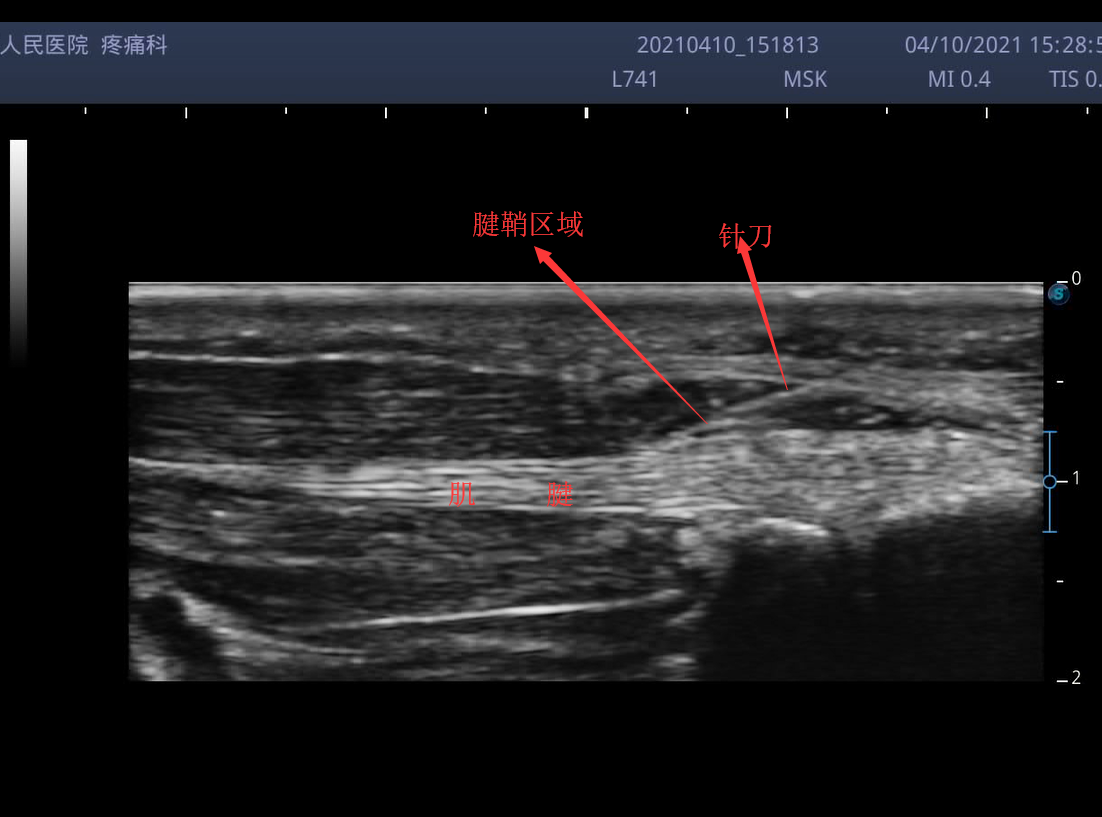

超声引导实现了这样的效果。在超声引导下实施狭窄性腱鞘的针刀治疗,能清晰的看到肌腱、增厚狭窄的腱鞘,针刀亦清晰可见,超声引导下实施狭窄性腱鞘的针刀治疗既发挥针刀的无痛苦、切口小的优点,又避免了误伤的风险了,使治疗可视化,真正做到扬长避短了。